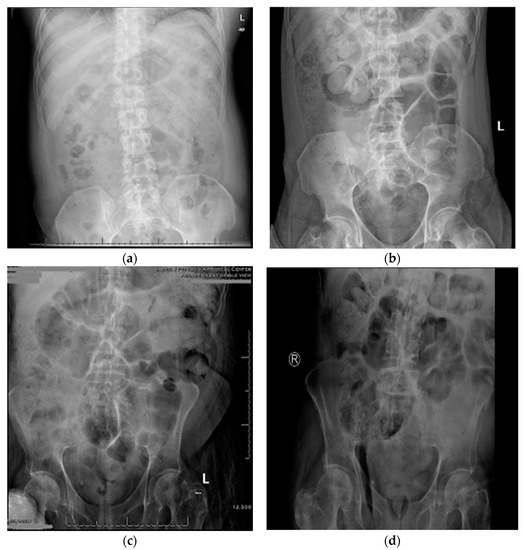

One-week SOC in six subjects consisted of 18 bowel care sessions, and the two-week SOC plus neostigmine and glycopyrrolate consisted of 36 bowel care sessions. At the conclusion of the SOC arm, the average length of time to complete a bowel care session was 107 ± 68 min, whereas at the termination of the SOC arm plus neostigmine and glycopyrrolate arm the average length of a bowel care session was markedly shortened to 41 ± 20 min (Figure 1; p < 0.0001); the difference in the length of bowel care between the control and drug-treatment arms ranged from 42 to 88 min (CI: 95%). After one-week of SOC, there was no significant change in body weight (0.33 ± 0.21 kg) and, as expected, no change in abdominal radiographic images of stool burden. In contrast, at the end of two weeks of SOC plus the dual drug-treatment, an average 2.8 ± 1.0 kg loss of body weight was observed (86 ± 25 kg vs. 83 ± 26 kg; p < 0.0001), with an initial 1.2 ± 1.2 kg loss of weight at the end of the first week. The values for individual weight loss after the dual drug intervention arm are provided (Table 1). The loss of body weight was confirmed on abdominal radiographs to be due to a reduction in retained stool (Figure 2). After two weeks of the dual drug treatment, the 10Q Survey showed an improvement in bowel care (Figure 3), and the Treatment Satisfaction Questionnaire for Medications revealed that the medications were well tolerated and that bowel care appeared to be improved as well (Figure 4).

The transdermal delivery of neostigmine and glycopyrrolate by iontophoresis substantially reduced the time to bowel evacuation in patients undergoing routine bowel care and resulted in a more complete stool evacuation, as determined by body weight and abdominal radiographic evidence. Subjectively, the patients showed improvement in all indicators of bowel care and were more satisfied with their bowel treatment regimens.

Figure 2. Representative qualitative measure of stool burden on abdominal radiograph after standard of care or standard of care plus neostigmine and glypyrrolate. Fecal burden: (a) marked stool throughout the colon, (b) moderate stool in the cecum; (c) moderate stool in the transverse and left colon, (d) moderate stool in the cecum. Loss of body weight after two weeks of standard of bowel care and the dual drug combination: (a,b), −4.4 kg; (c,d), −2.6 kg.